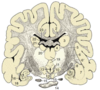

Label the diagram

Describe CSF formation, drainage and function